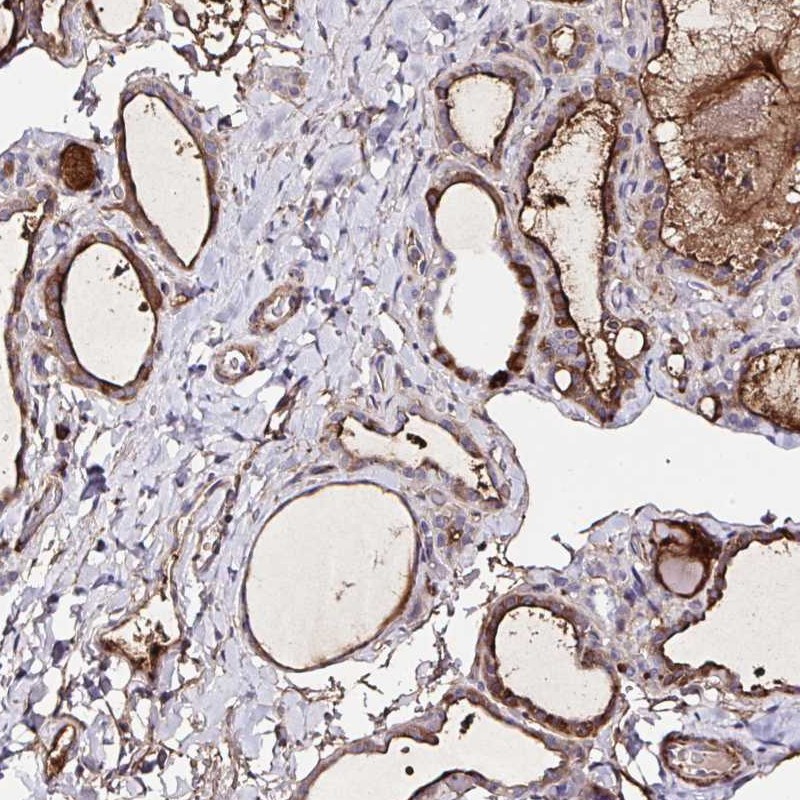

Immunohistochemical staining of human thyroid gland shows strong cytoplasmic positivity in glandular cells.